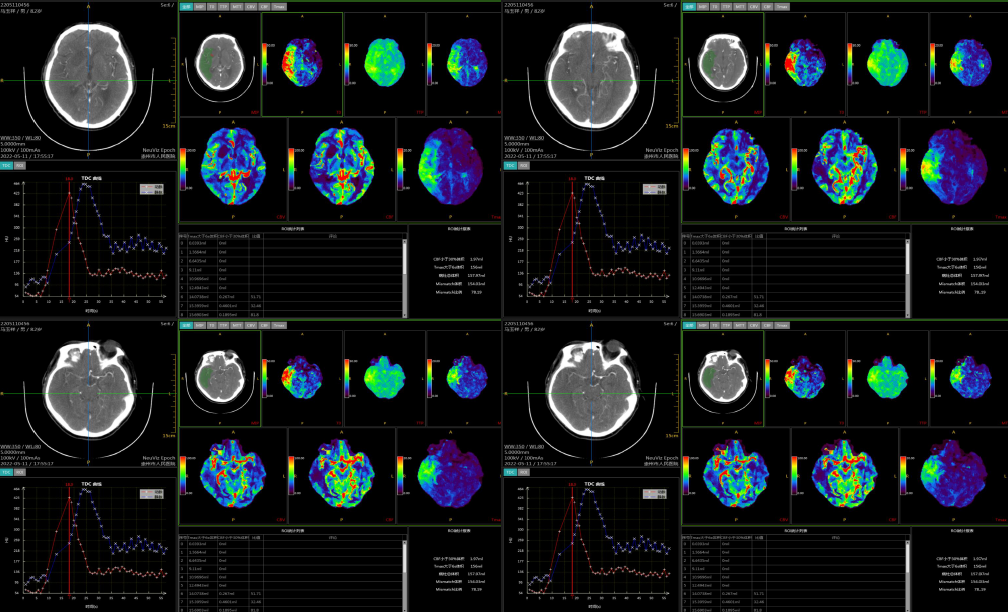

脑灌注成像

病历夹什么径技·第152期|串联营病历夹:川陕大营_https://www.jmylbn.com_新闻资讯_第43张

病历夹什么径技·第152期|串联营病历夹:川陕大营_https://www.jmylbn.com_新闻资讯_第44张

病历夹什么径技·第152期|串联营病历夹:川陕大营_https://www.jmylbn.com_新闻资讯_第45张

<<滑动查看下一张图片>>

诊断:右侧额顶颞叶及基底节区局部血流灌注减低,请结合临床。